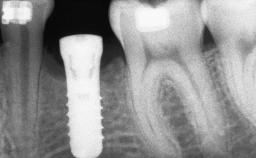

A 20-year-old woman was referred for implant therapy in 2004. Her medical history revealed no significant findings, and neither did she smoke nor take any medications. An extraoral examination revealed no abnormalities of the skin, hair or nails. The intraoral examination revealed only 11 permanent teeth clinically. These were normal in shape, size, and color. In addition, eight retained deciduous teeth (53, 62, 63, 71, 72, 73, 81, 82) were present. No abnormalities were detected during the general examination. The family history revealed that the patient’s father and two sisters were on record with similar conditions. The clinical examination revealed a thick gingival biotype. No recession of the attached gingiva was noted, but the retained deciduous teeth were mobile and unsightly. As a syndrome had not been diagnosed, the case was categorized as non-syndromic oligodontia.

| Type of Implants | One-Piece|Reduced-Diameter |

| Placement Protocol | Early or late implant placement |

| Bone Volume | Deficient horizontally, requiring prior grafting |